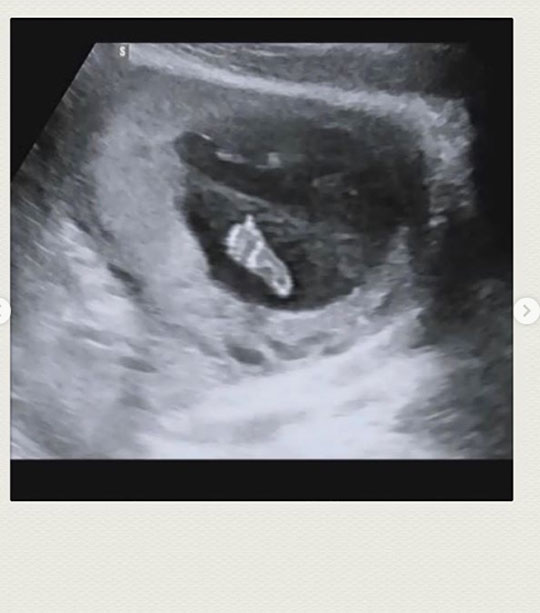

구재이는 22일 오후 자신의 인스타그램에 초음파 사진과 함께 “갑자기 찾아와 깜짝 놀라게한 리보”라며 아이의 태명을 소개했다. 이어 “아직은 모든 것이 낯설고 새롭고 놀라움의 연속이지만 건강하게 16주 차를 지나면서 잘 자라고 있어 감사한 마음뿐이다”라고 덧붙였다.

구재이는 “반가워 리보야”라고 덧붙이며 임신의 기쁨과 설렘을 다시 한번 만끽했다. 이에 팬들과 지인들은 축하 메시지를 전했다.

갑자기 찾아와 깜짝 놀래킨 리보

아직은 모든것이 낯설고 새롭고 놀라움의 연속이지만

건강하게 16주를 지나며 잘자라고 있어 감사한 마음뿐이네요.

반가워 리보야